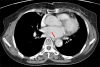

Dysphagia aortica is a rare etiology of dysphagia resulting from extrinsic compression of esophagus by thoracic aortic aneurysm or tortuosity and elongation of thoracic aorta. The clinical findings resemble those of esophageal malignancy or esophageal motility disorders. Therefore, primary diagnosis of dysphagia aortica is very difficult. We, herein, report a case of dysphagia aortica aggravated by wearing the abdominal binder in a 70-year-old woman and review the literature pertaining to this condition. Dysphagia aortica should be considered in the differential diagnosis of dysphagia.